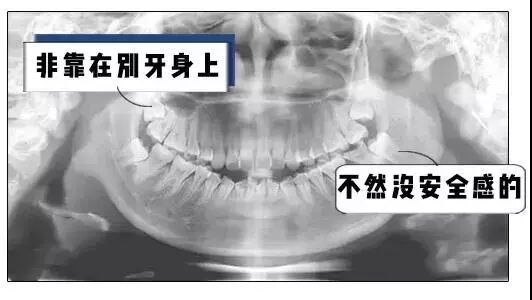

一般人的智齿长这样

这样

还有这样

只有你想不到

没有它做不到

它不好好长就算了

长的不好还骚扰隔壁邻居

遇到这种智齿

别犹豫